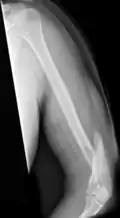

| Midshaft humerus fracture with callus formation | |

A humerus fracture is a break of the humerus bone in the upper arm.[1] Symptoms may include pain, swelling, and bruising.[1] There may be a decreased ability to move the arm and the person may present holding their elbow.[2] Complications may include injury to an artery or nerve, and compartment syndrome.[2]

The cause of a humerus fracture is usually physical trauma such as a fall.[1] Other causes include conditions such as cancer in the bone.[2] Types include proximal humeral fractures, humeral shaft fractures, and distal humeral fractures.[1][2] Diagnosis is generally confirmed by X-rays.[2] A CT scan may be done in proximal fractures to gather further details.[2]

Treatment options may include a sling, splint, brace, or surgery.[1] In proximal fractures that remain well aligned, a sling is often sufficient.[2] Many humerus shaft fractures may be treated with a brace rather than surgery.[2] Surgical options may include open reduction and internal fixation, closed reduction and percutaneous pinning, and intramedullary nailing.[2] Joint replacement may be another option.[2] Proximal and shaft fractures generally have a good outcome while outcomes with distal fractures can be less good.[2] They represent about 4% of fractures.[2]